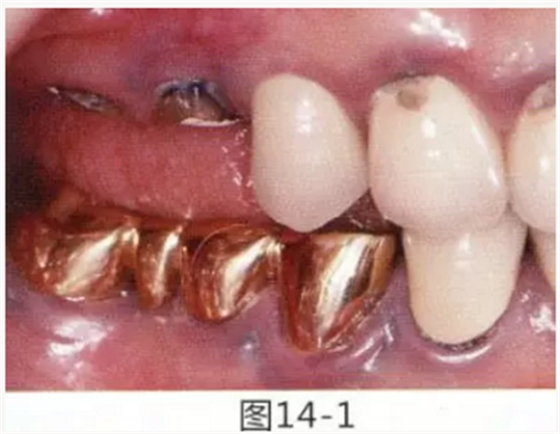

病例5

為了提高對修復體的術后效果,以生物學寬度,獲取附著齦為目的進行游離齦移植的病例

圖14-1 修復體周圍角化牙齦較少,很難進行清潔的狀態(tài),并有緣下齲壞的發(fā)生。

圖14-2,3 徹底去除齲壞后,試圖通過游離齦移植獲取生物學寬度和附著齦。

圖14-4~6修復體周圍角化牙齦較少,很難進行清潔的狀態(tài),并有緣下齲壞的發(fā)生。

圖14-7 配戴最終修復體完成5年后的狀態(tài)。保持良好。